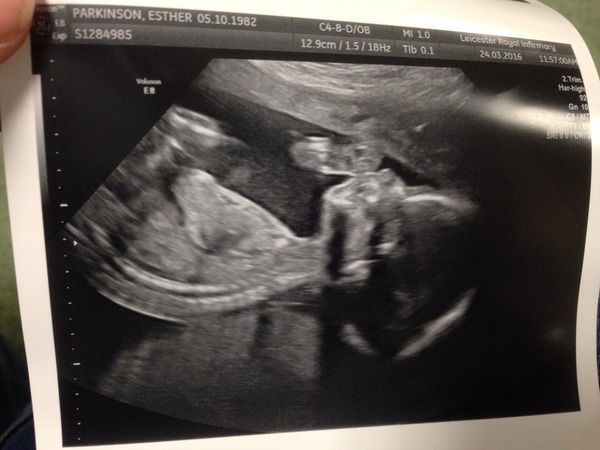

Just caught up, gosh what a tough time lily, pleased the procedure went well and hoping baby stays put til the end!

Had my scan today, had to have an internal as they couldn't see my cervix because of how baby was lying, and I'll also be joining the low placenta club. She said it wasn't completely covering it, but was too close, so they're just going to check again at 32 weeks. She did say they would do it at 36, until I told her that two of my babies were born at 36 weeks! I'm sure it will have moved out of the way as others have said-it's nice to get another look at the baby. I always find it such a long time after the 20 week scan til they're actually born so nice to get an extra one.

Still not feeling any movements, could see it moving on the screen but couldn't feel a thing. Must have too much flab in the way!

Stayed team yellow too, the sonographer told us when to look away so didn't even get a peek to guess.

Here's our little thumb sucker anyway Smile